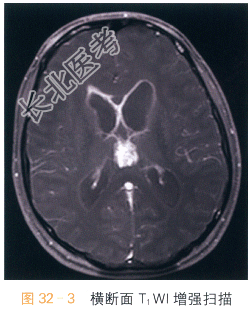

读片分析:头颅横断面T₁WI、T₂WI示松果体区不规则软组织肿块影,呈T₁WI等高、T₂WI低信号影,信号不均匀;横断面、矢状面T₁WI增强扫描可见病灶明显强化,室管膜亦可见明显强化。